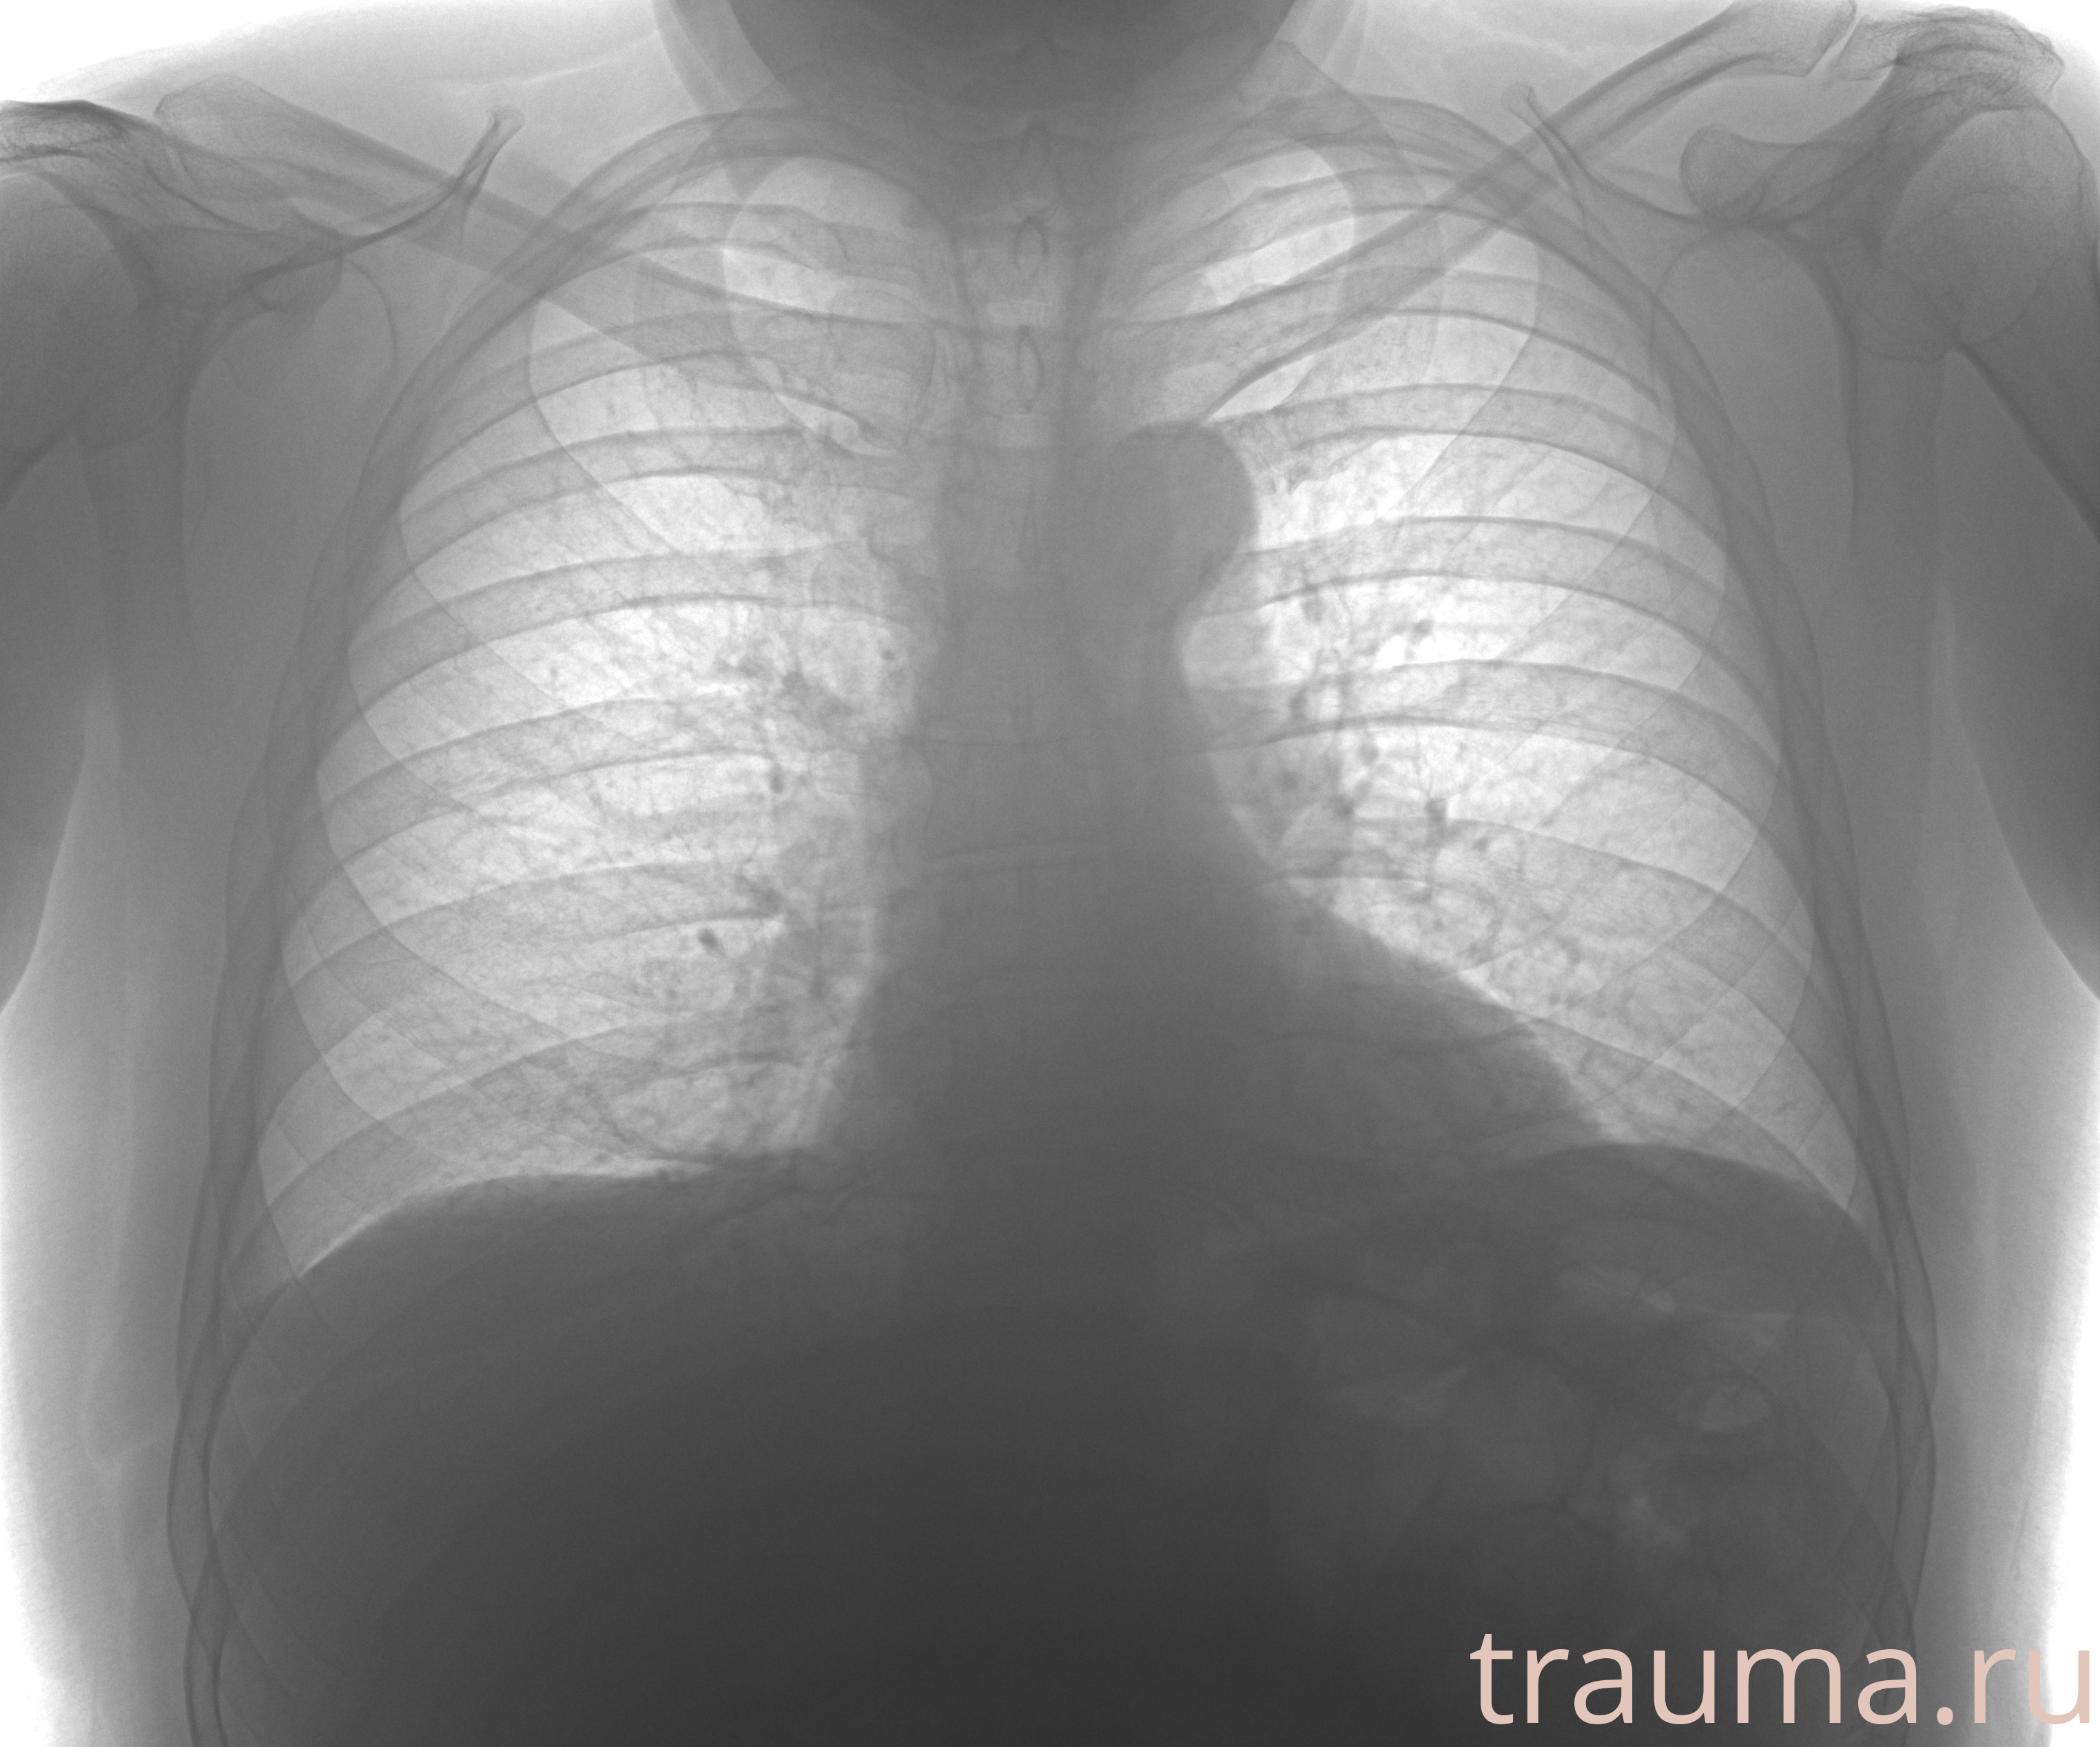

Рентгенограммы

Рентген на дому: по вашему адресу приезжает врач-рентгенолог, травматолог-ортопед с мобильным рентгеновским аппаратом, проводит диагностику травмы или заболевания, делает необходимые рентгенограммы, дает рекомендации по дальнейшему лечению. Получить качественные снимки в домашних условиях возможно благодаря уникальной методике, разработанной МосРентген Центром для института  Склифосовского

при переломе шейки бедра и пневмонии от компании МосРентген Центр - партнера Института имени Склифосовского